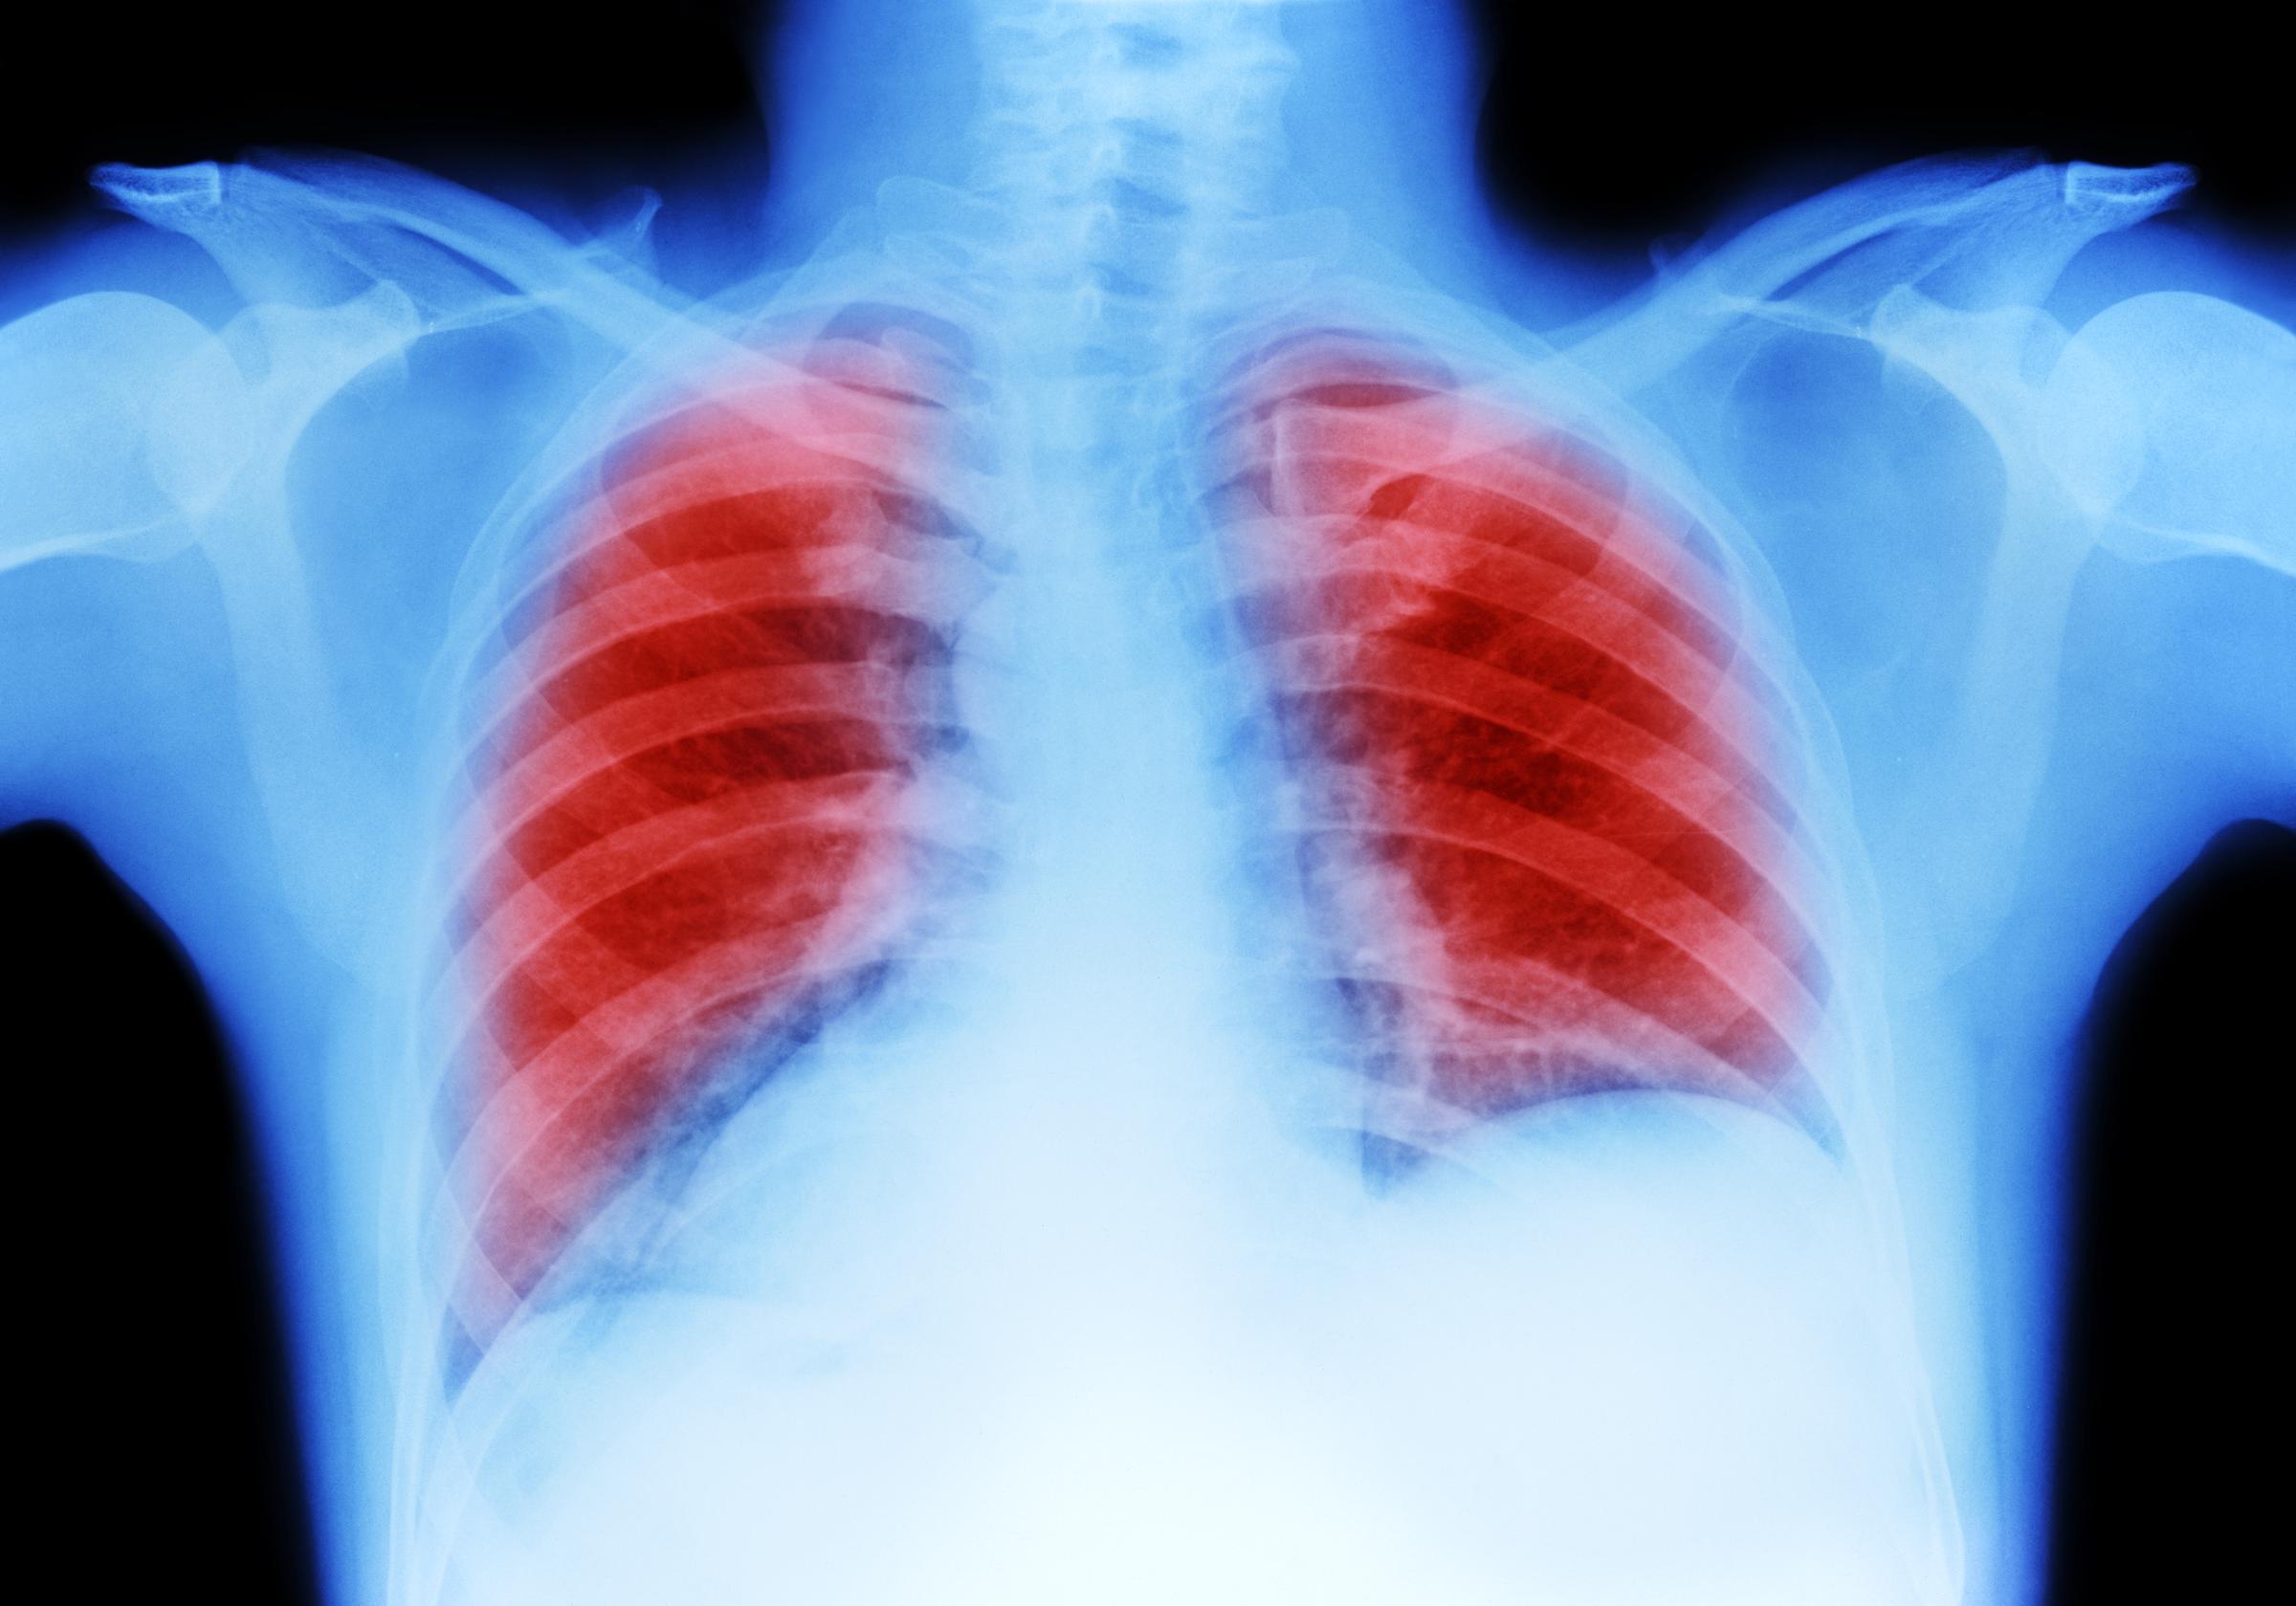

Una radiografía de pulmones | Fuente: Pixabay

Una radiografía de pulmones | Fuente: Getty Images